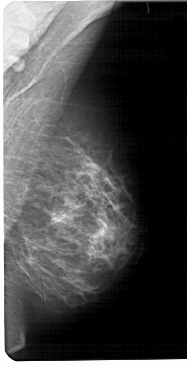

A_1470_1.RIGHT_MLO

RIGHT_MLO LINES 5491 PIXELS_PER_LINE 2791 BITS_PER_PIXEL 12 RESOLUTION 43.5 NON_OVERLAY